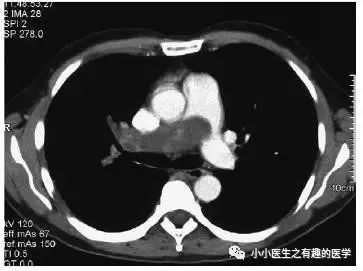

法兰西报道的一个患者。

这么大一个血栓!

好大的一条血栓!然而,最终做了手术,病理如下:

五颜六色的,好好看啊。然而,this is 肺动脉内膜肉瘤。仔细看看,不对。

充盈缺损的地方,密度不均匀,并且有强化,血栓里面没有血管,一般不会强化,所以有可能是肿瘤。